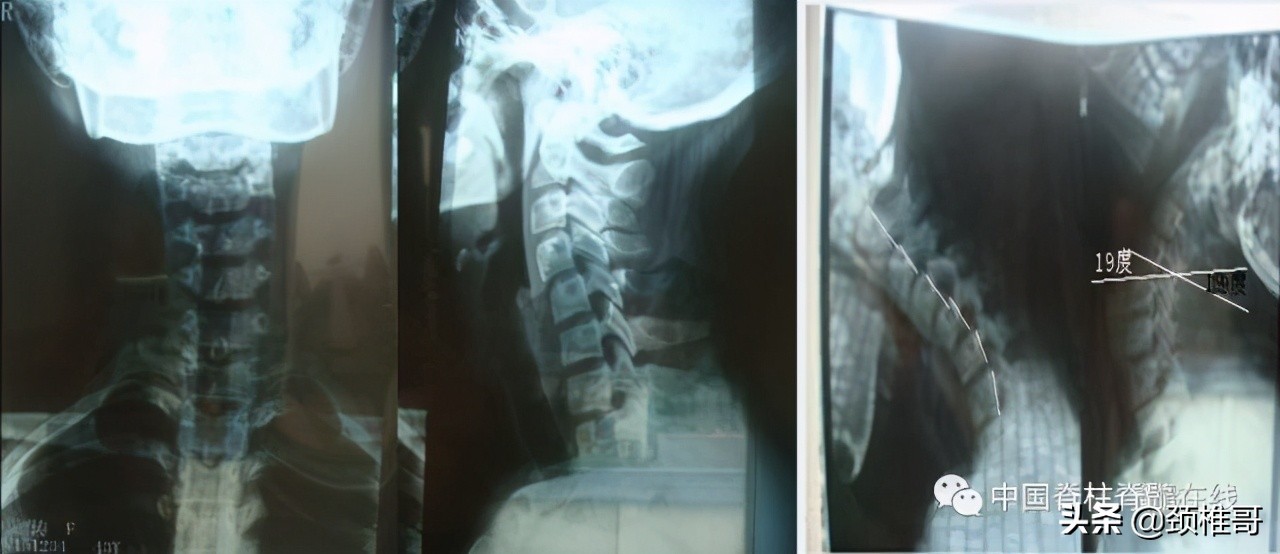

再看看这个病人,头晕2年,转头、低头时头晕加重,他的核磁共振显示椎间盘退变,水分减少了,但是没有明显的椎间盘突出,充其量算是膨出,但是我们看看他的x线片:颈椎3-5棘突序列不整齐,侧位显示颈椎5/6之间夹角增大,过伸位片显示,颈椎4-7各个节段夹角都超过了11°。过屈侧位片显示5、6、7三个节段出现了双边征,是椎体发生了旋转不稳的结果。这个病例的主要问题在于椎间盘吗?不对,在于肌肉和韧带对于颈椎4-7各个节段之间的稳定控制能力的减退。

正位:颈椎序列欠佳 侧位:颈椎4-7夹角增大

对节段颈椎成角过大、双边征

MRI显示颈椎多节段椎间盘退变膨出